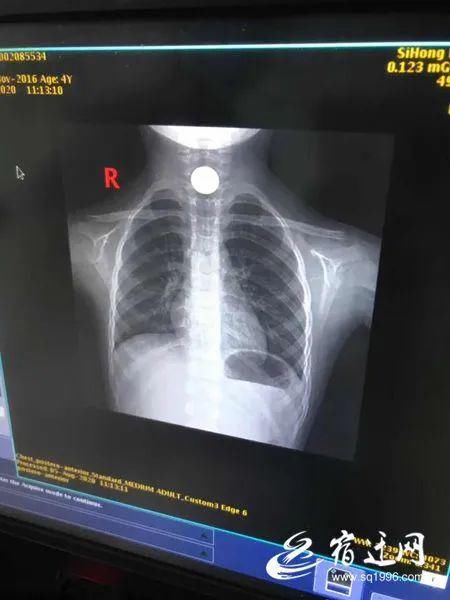

8月5日,泗洪县一名3岁的小女孩阿四和姐姐玩耍时,误将一枚一元硬币吞了下去。听到哭声的阿四爸妈赶紧把孩子送去医院,经过26小时,才把这枚硬币顺利排出体外。

医生了解情况后建议继续观察,看孩子是否能够通过自主排便将硬币排出体外。如果实在不行,再进行手术。惠女士带着孩子办理了住院手续,并拍了片子。

惠女士说,到了晚上孩子说喉咙不难受了,于是医生又建议拍片子再看看情况,后来发现硬币已经顺着食道进入了孩子的胃里。最后,阿四通过排便,把硬币排了出来,已经转危为安。